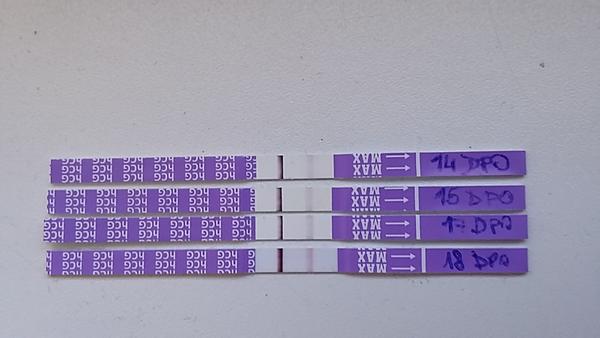

Těhotenský test. Dávám fotku. Co myslíte?

Holky uz jsem z toho zmatena. Dnes test negativni, spletla jsem se nejspis budu az dnes 13 DPO ovulku jsem mela az 20 DC a odpoledme na toaletaku jemne zaspineni. Myslite, ze by se mohlo jeste jednat o zahnizdovani? Jak bych to mela ted s ms, kterou uz bych dnes mela mit? Dekuji moc za odpovědi!!

@veronika334 ja jsem právě 17Dpo a tři dny zpoždění a carka postupne sili ale furt ještě není úplne na max. Clear Blue mam už v šuplíku nachystaný počkám ještě cca týden jestli nedorazí ms a pak udělám ;)

@pandabox ze zvyku :D , ze zvědavosti, jestli 10DPO je fakt duch vidět, kdy třeba bude vidět u mě... je to napínavé, jako když stíráš hrací los a čekáš jestli vyhraješ... Je to návykové, podle mě nedám pokoj, dokud tam dvě nebudou... no a asi taky proto, že ještě nebylo zklamání z bílého testu tak velké, aby se mi pohnula mysl a řekla si, že testovat už budu až po termínu MS. 🙂 .. penízky za testy mě zatím netrápí mám každý měsíc 600,- od zaměstnavatele do lékárny a nikdy jsem to na nic nevypotřebovala, tak teď to mám za co utrácet :D

@sunny1sis 10 dpo. Budu na startovni care v loveni duchu. ☺